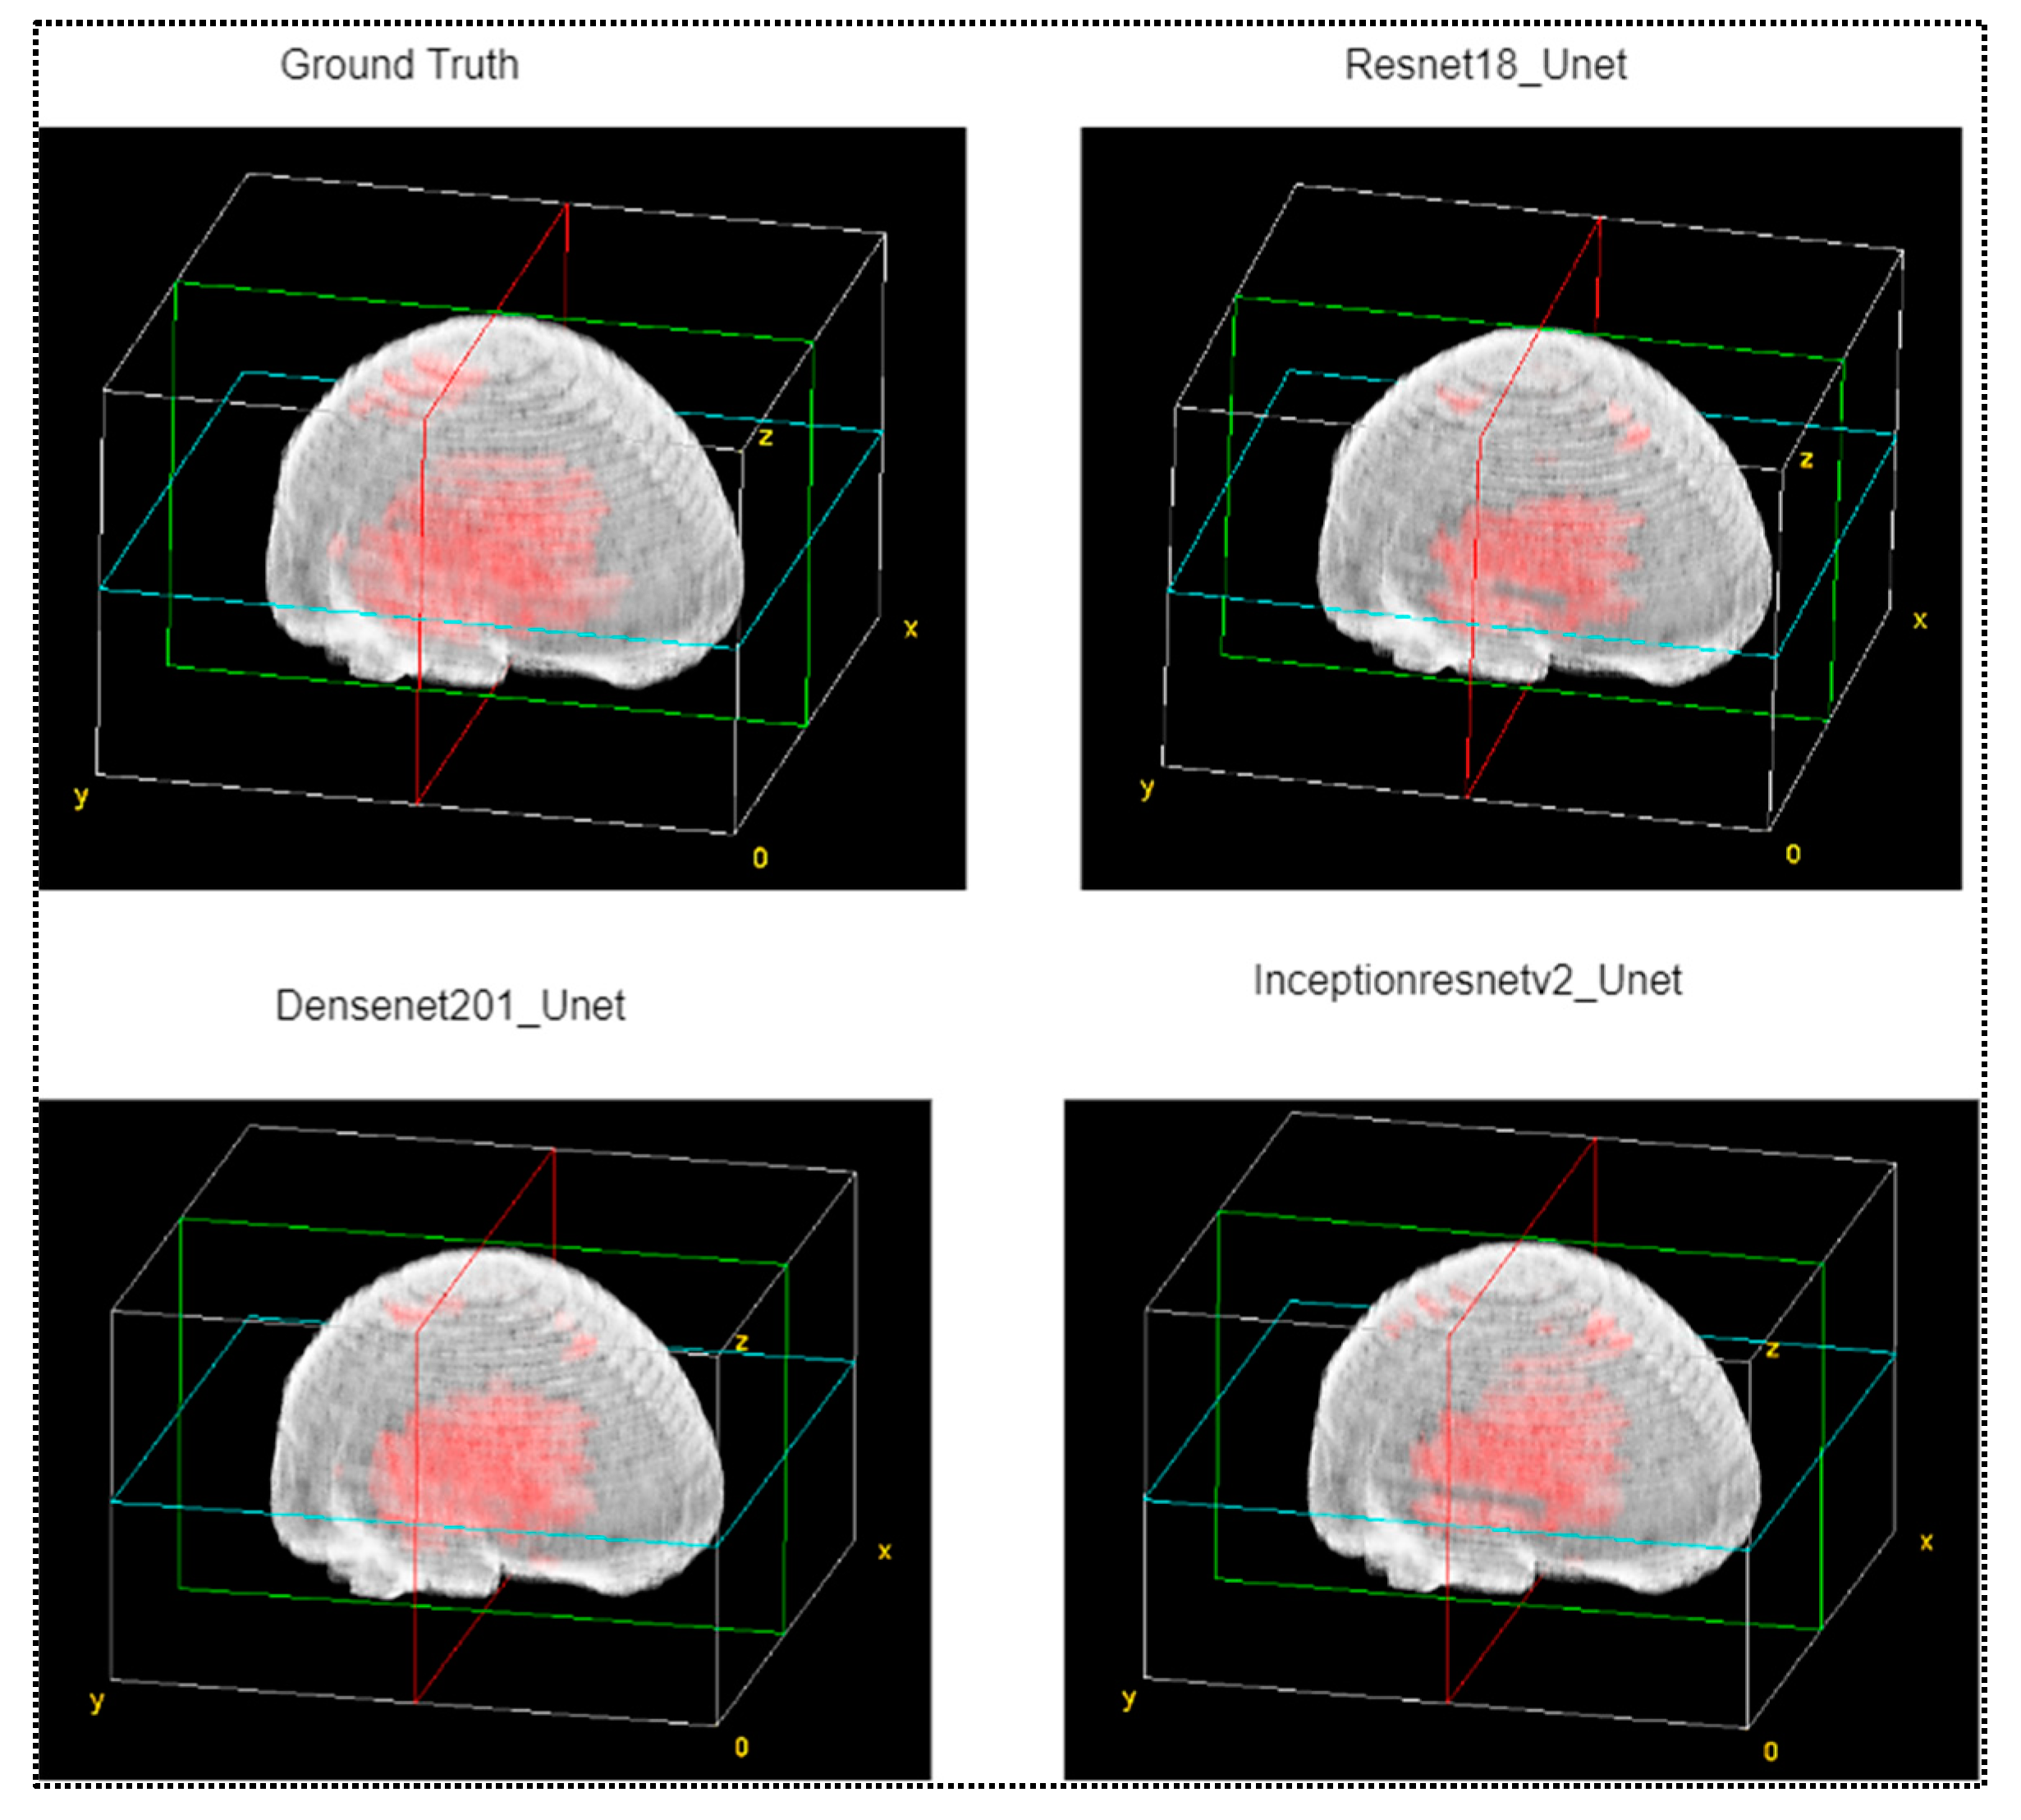

- This work presented a 3D visualization tool to show the hemorrhage in the CT volume predicted using the proposed technique and compare it with a ground truth hemorrhage annotated by the experts.

3.2. Reconstruction of 3D Models of ICH